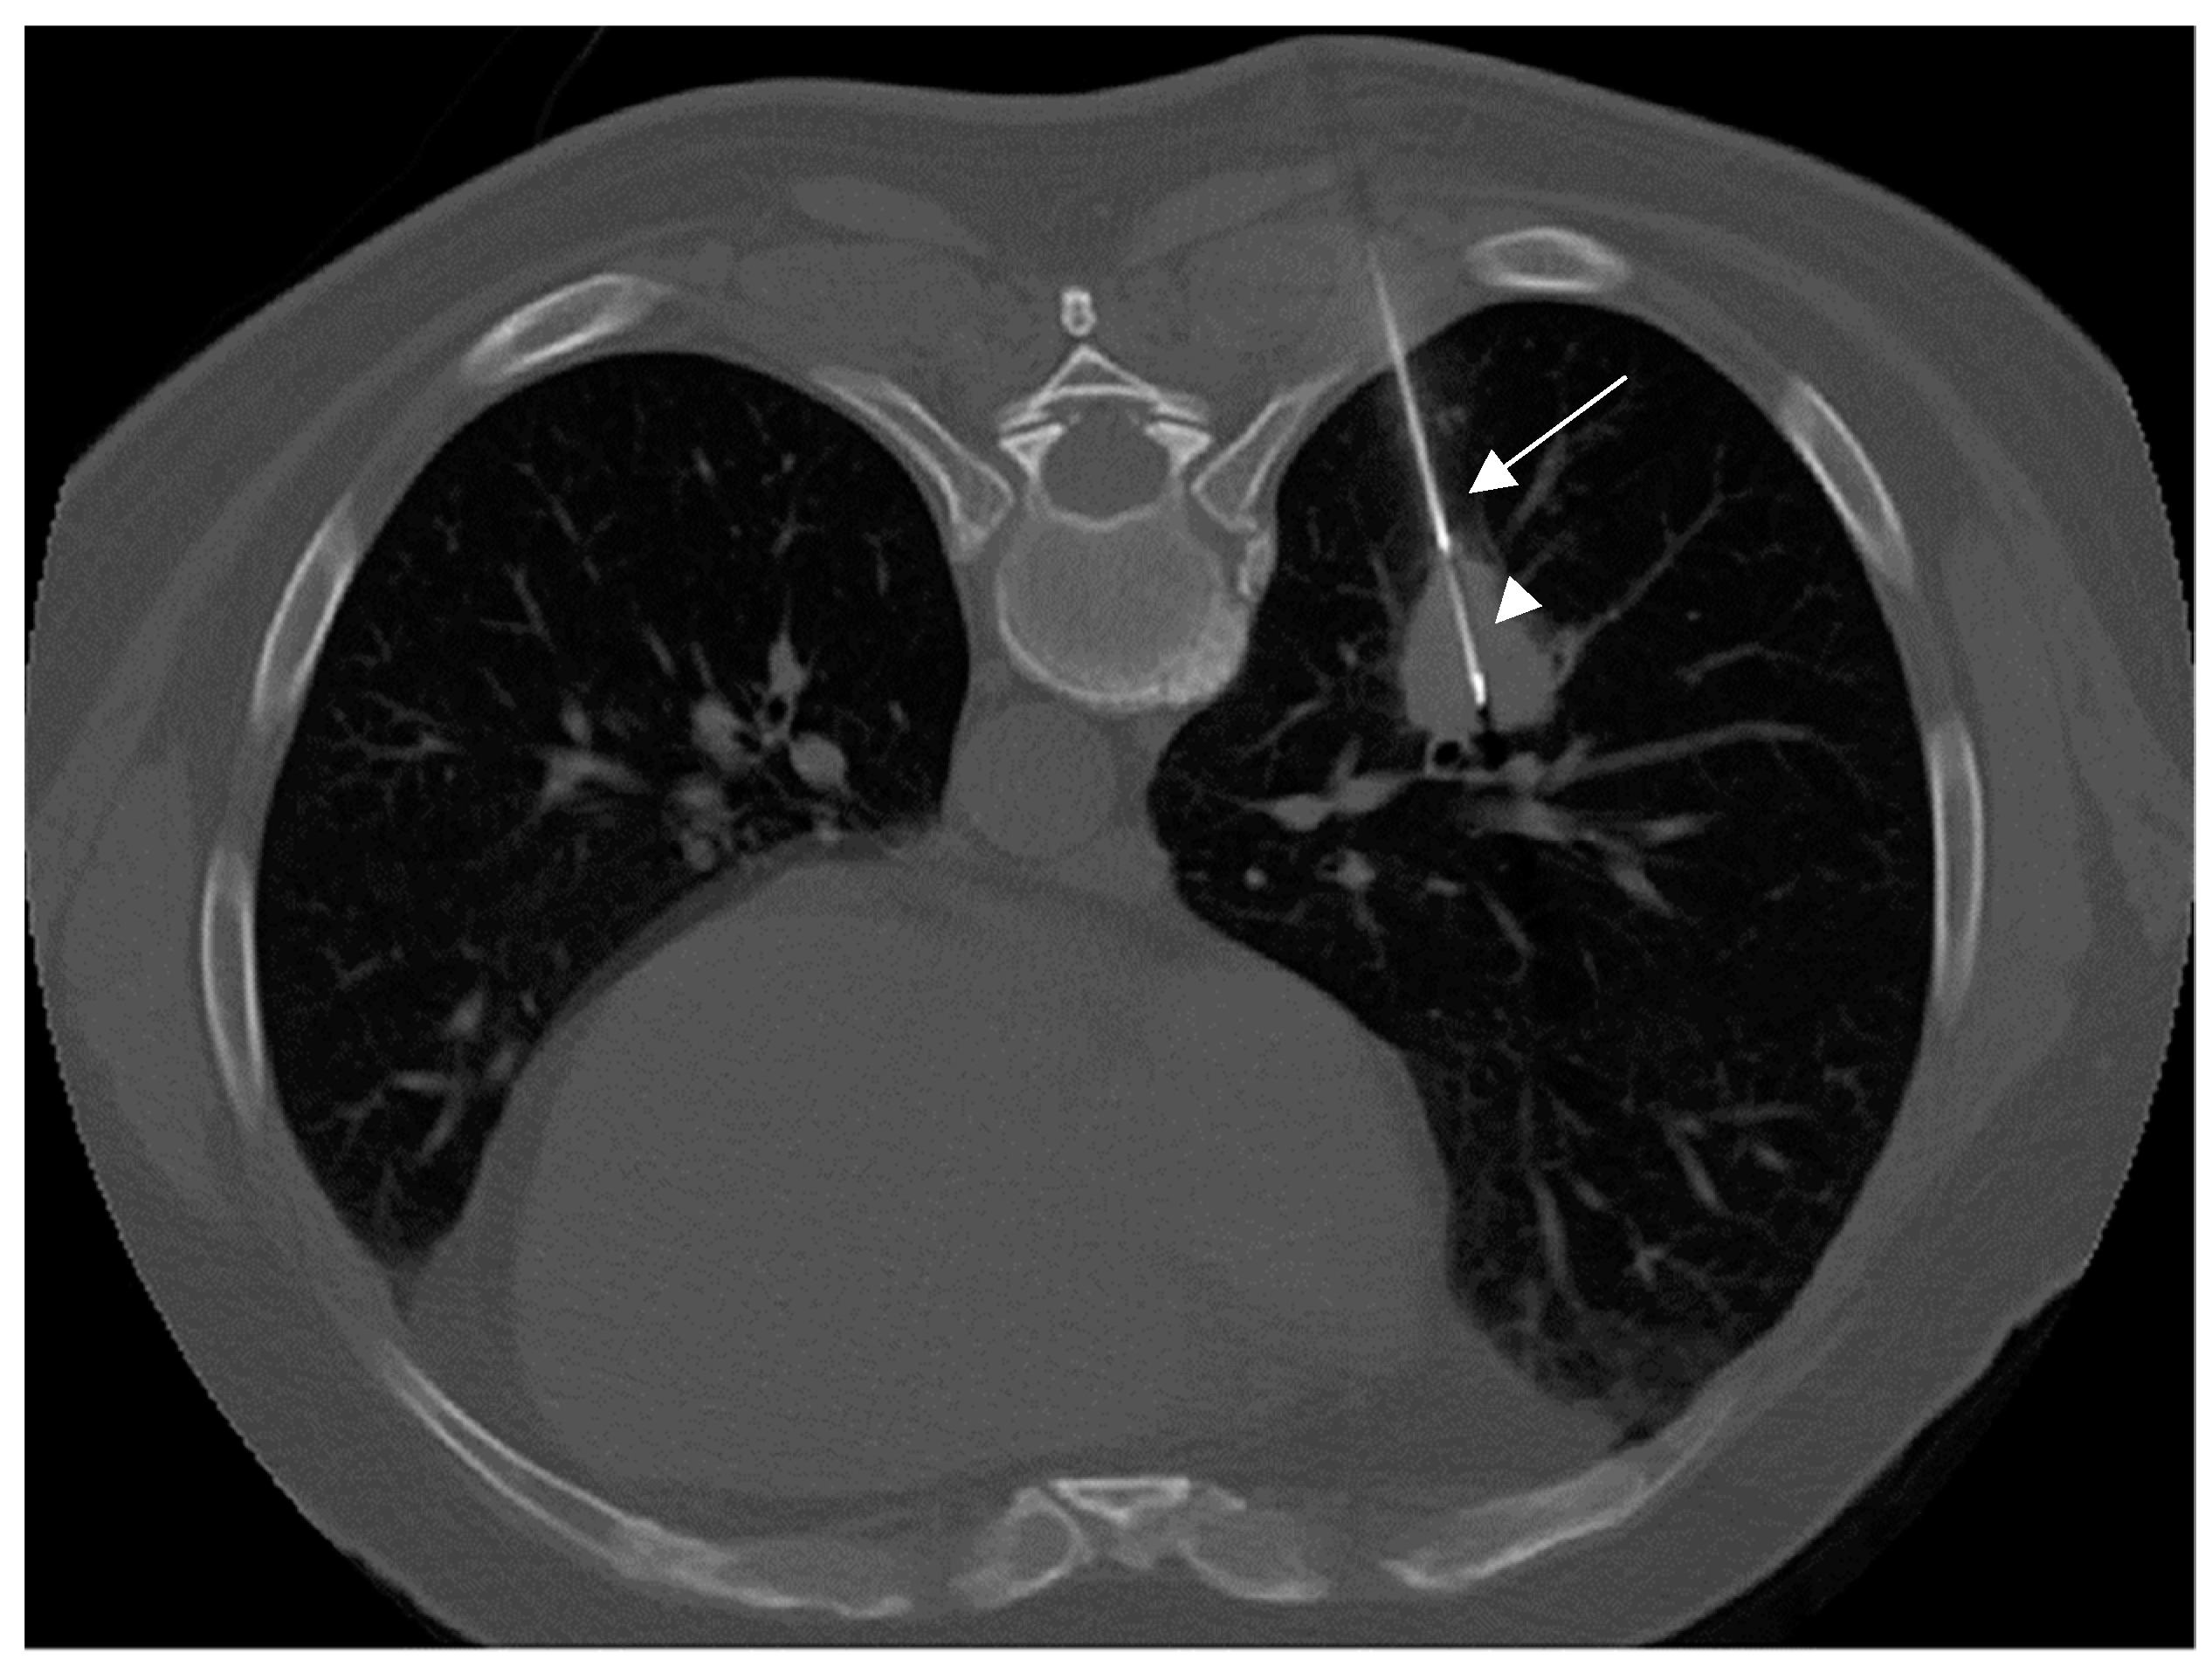

2.2. Biopsy Technique